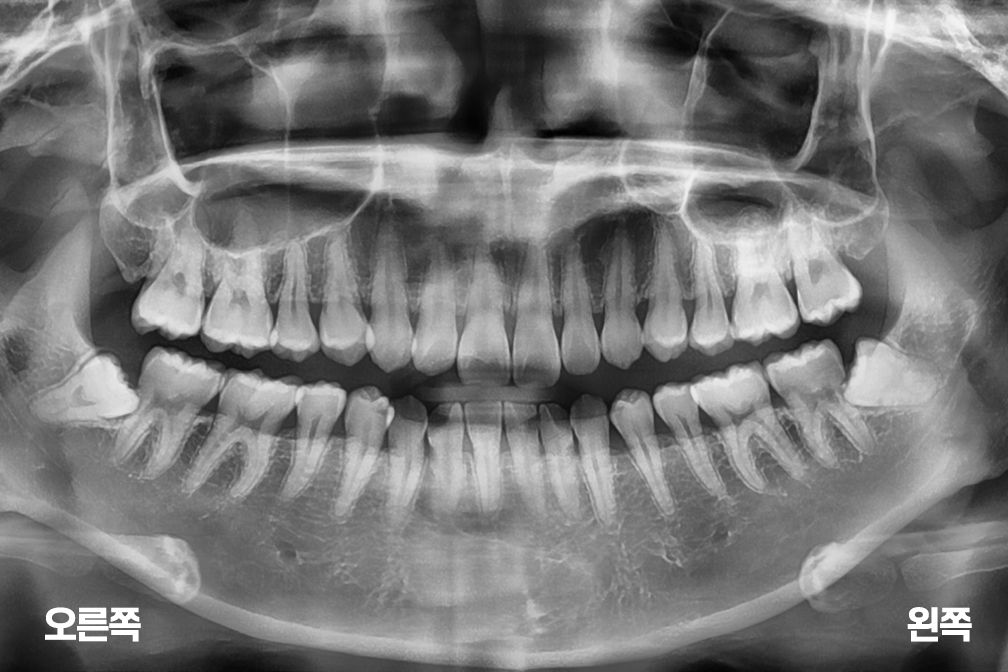

사랑니발치 아래 양쪽 사랑니 발치

사랑니 발치